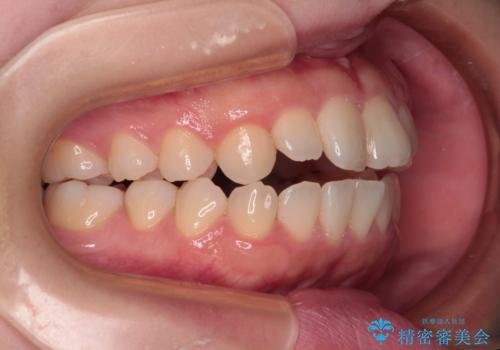

- 前歯が開いて飛び出していることを気にして来院された患者様です。

舌の突出癖により上下前歯は接触できず、更には前方に押し出されて出っ歯になっている状態でした。

上下左右の第一小臼歯4本を抜歯し、ワイヤー装置での抜歯矯正を行っていくのですが、原因である舌の突出癖を改善しないことには治療がうまく進められないため、舌のトレーニングを徹底するよう指導していくこととしました。